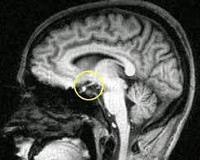

Послеродовой некроз гипофиза — так ещё называют синдром Шихана. История болезни свидетельствует о том, что это достаточно сложная патология, которая развивается после тяжёлых и длительных родов. Причиной становится обильное кровотечение, которое, в свою очередь, приводит к артериальной гипотонии. Вследствие её развития меньше снабжается кровью гипофиз — маленькая железа в головном мозге, что отвечает за работу эндокринной системы человека и выработку гормонов. В организме развивается синдром Шихана, последствия которого не самые приятные — вы не сможете кормить малыша грудью, но это только самая малая часть проблем, что ожидают маму.

Это механизм от самого зарождения недуга до ярких проявлений симптомов. Опытные врачи рассматривают его на различных уровнях: от молекулярных патологий до нарушения работы организма в целом. Изучать его необходимо, так как именно патогенез даёт ответ на вопрос о том, как и почему развивается недуг. Что касается синдрома Шихана, то давно установлено: его основное проявление заключается в некротических изменениях в гипофизе. Они возникают на фоне свёртывания крови, когда наблюдается спазм сосудов передней доли гипофиза после сильной кровопотери.

Ключевое звено в развитии синдрома Шихана — несоответствие между потребностью гипофиза в кровоснабжении и объемом поступающей крови. У беременных отмечается физиологичное увеличение размеров гипофизарной ткани на 120-136%, связанное с необходимостью вынашивания плода и подготовки организма женщины к родам. В первую очередь гипертрофируются и гиперплазируются лактотропоциты — клетки, секретирующие гормон пролактин, под действием которого развивается и готовится к выработке молока ткань молочных желез. При этом кровоток в органе остается неизменным, поэтому гипофиз становится особенно чувствительным к нарушениям кровообращения. Гиповолемические и коагулопатические кровотечения, возникающие во время родов, приводят к дефициту кровоснабжения железистой ткани, что сопровождается вазоконстрикцией и последующим белым инфарктом с коагуляционным некрозом. В результате гибели клеток прекращается выработка гормонов передней доли гипофиза, что формирует типичную клиническую картину болезни Шихана.

- Методы медицинской визуализации. Прицельный рентгенологический снимок турецкого седла позволяет выявить уменьшение размеров железы. Более подробную информацию о структуре и изменениях органа предоставляют томографические методики (МРТ, компьютерная томография).